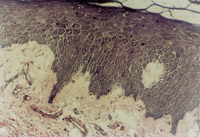

伤后12h急诊入院,检查双下肢为浅Ⅲ度烧伤。创面表皮已坏死剥脱,真皮层变性坏死呈蜡黄色和蜡白色相间(图5-3-1)。取局部组织做病理切片检查,显示上皮组织全层坏死,真皮层胶原纤维变性,结构紊乱,微循环瘀滞(图5-3-2)。

5-3-1 李某 女 20岁,汽油烧伤35%TBSA (深Ⅱ°深型15%,浅Ⅲ°20%)

5-3-2 上皮组织全层坏死,胶原纤维变性,微循环瘀滞 HE×20